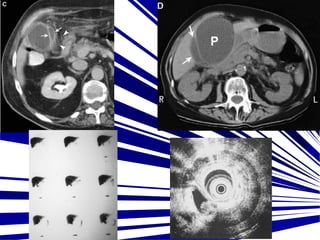

• #21 CT shows an enhancing rim around the fluid (arrows) and inflammatory edema in the adjacent fat (arrowheads). (D) CT of the pancreatic pseudocyst (P) displacing the gallbladder (arrows). HIDA SCAN normal, capta medio de contraste Ultrasonido endoscopico con litos en la vesicula biliar